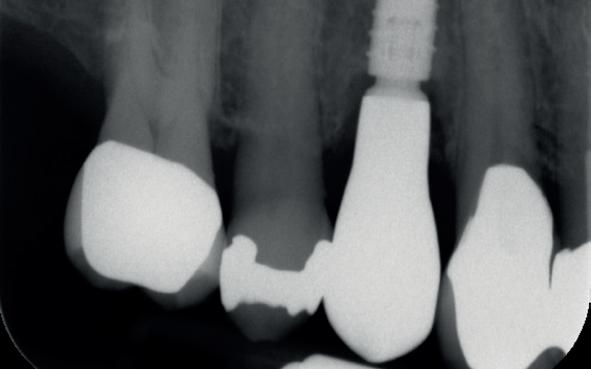

In deze casus is extractie van de 37 geïndiceerd in verband met een fistel en restpockets, zoals zichtbaar op de röntgenfoto’s (afbeelding 1). Duidelijk te zien is de forse peri-apicale ontsteking en het botverlies bij de 37, dat zowel richting buccaal als linguaal doorloopt. De 37 wordt atraumatisch verwijderd. Er is aan de linguale zijde veel bot verloren en er is sprake van een perforatie aan de buccale zijde.

Er wordt besloten om botmateriaal te plaatsen in de extractie-alveole. Vervolgens wordt het afgesloten met een titanium versterkt d-PTFE membraan (afbeelding 2). Na vier weken wordt het membraan verwijderd.

Zes maanden na extractie wordt het implantaat 37 geplaatst. Er is sprake van een goede genezing en de processushoogte en -breedte zijn behouden en opgebouwd. Ook is er zichtbaar gekeratiniseerd weefsel

1 2 Ridge preservation met d-PTFE membranen 35

gewonnen. De wond kan na het plaatsen van een healing abutment primair gesloten worden (Afbeelding 3a-3d).

In afbeeldingen 4a-c is het resultaat drie maanden na het plaatsen van het implantaat te zien. De genezing is volledig en de verwijzer kan de suprastructuur vervaardigen (afbeelding 4a-4c).

In afbeeldingen 5a-d is de implantaatkroon 37 te zien, twee jaar na plaatsing. Op de röntgenfoto is herstel van zowel corticaal als spongieus bot te zien. (De CB-CT was vervaardigd in verband met implantologische indicatie in het naastliggende gebied).

Deze casus illustreert dat er op een voorspelbare manier een ridge preservation procedure uitgevoerd kan worden met een d-PTFE membraan en er daarna voorspelbaar geïmplanteerd kan worden.